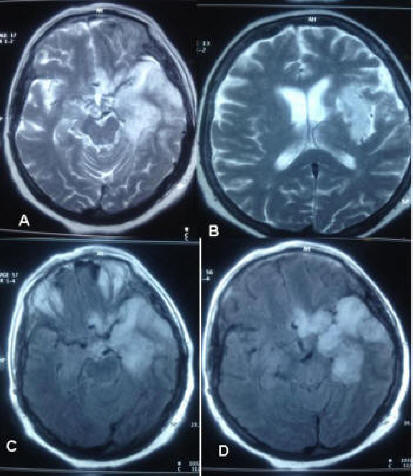

CASE REPORT Open Access Neurosyphilis With Dementia And ...

CASE REPORT Open Access Neurosyphilis with dementia and bilateral hippocampal atrophy on brain magnetic resonance imaging Shima Mehrabian 1*, Margarita Raycheva 1, Martina Traykova 1, Tonya Stankova 1, Latchezar Penev 2, ... View Full Source